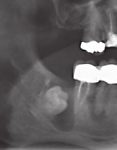

Retinierter Zähne

Wir bieten routinierte Entfernung retinierter Zähne. Bei besonders schwieriger anatomischer Lage (direkte Lage am n.alveolaris inferior) bieten wir durch Einsatz piezochirurgischer Osteotome die derzeit weichgewebs-schonendste Methode der Entfernung insbesondere der unteren Weisheits-zähne an.

Der Einsatz eines Chirurgielasers und eine direkte postoperative photodynamische Softlaserbehandlung minimieren die postoperativen Beschwerden unserer Patienten.

Auch die Freilegung retinierter Zähne zur anschließenden

kieferorthopädischen Eingliederung in die Zahnreihe wird im Bedarfsfall durch den Einsatz piezochirurgischer Präparationsmethoden durchgeführt.